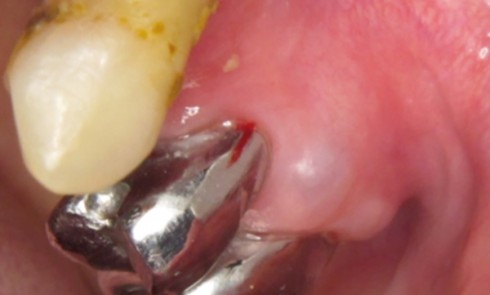

Article réservé à nos abonnés Péri-implantite et cancer

Dans un récent numéro de L’Information Dentaire était évoqué le problème des relations entre péri-implantite et cancer sous le titre...